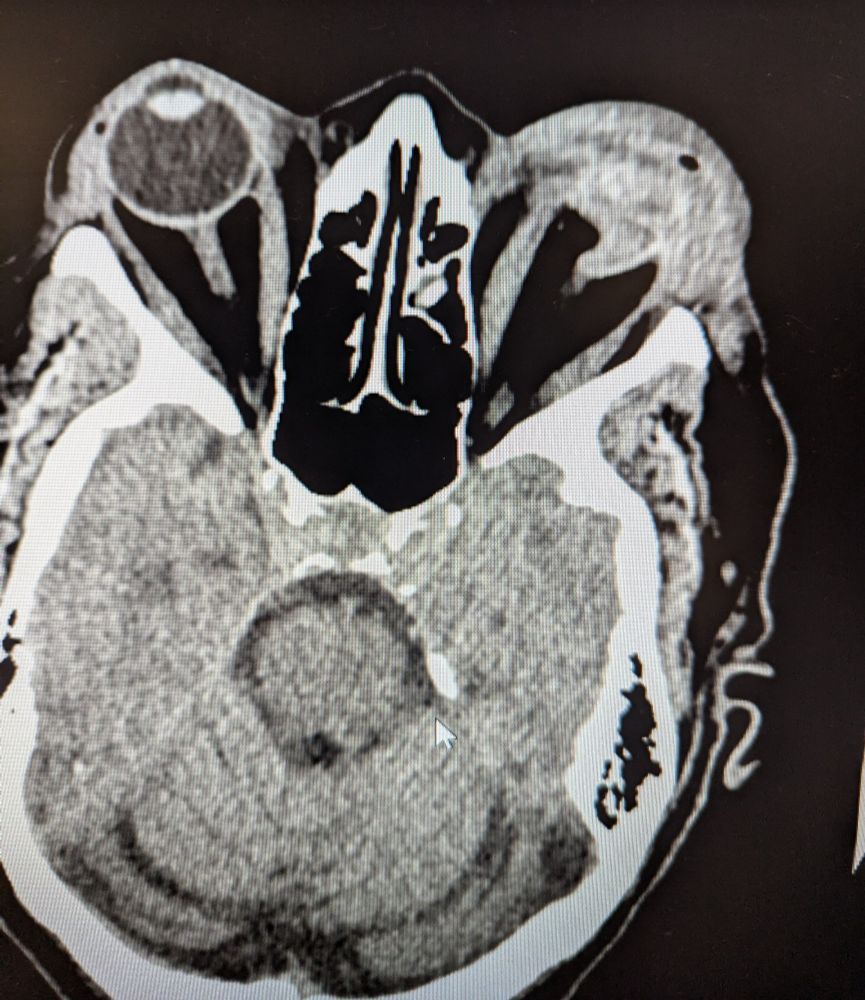

What do you think the cause is of this spontaneous cerebellar hemorrhage in a young female?

#medsky

#nuerosky

#radsky